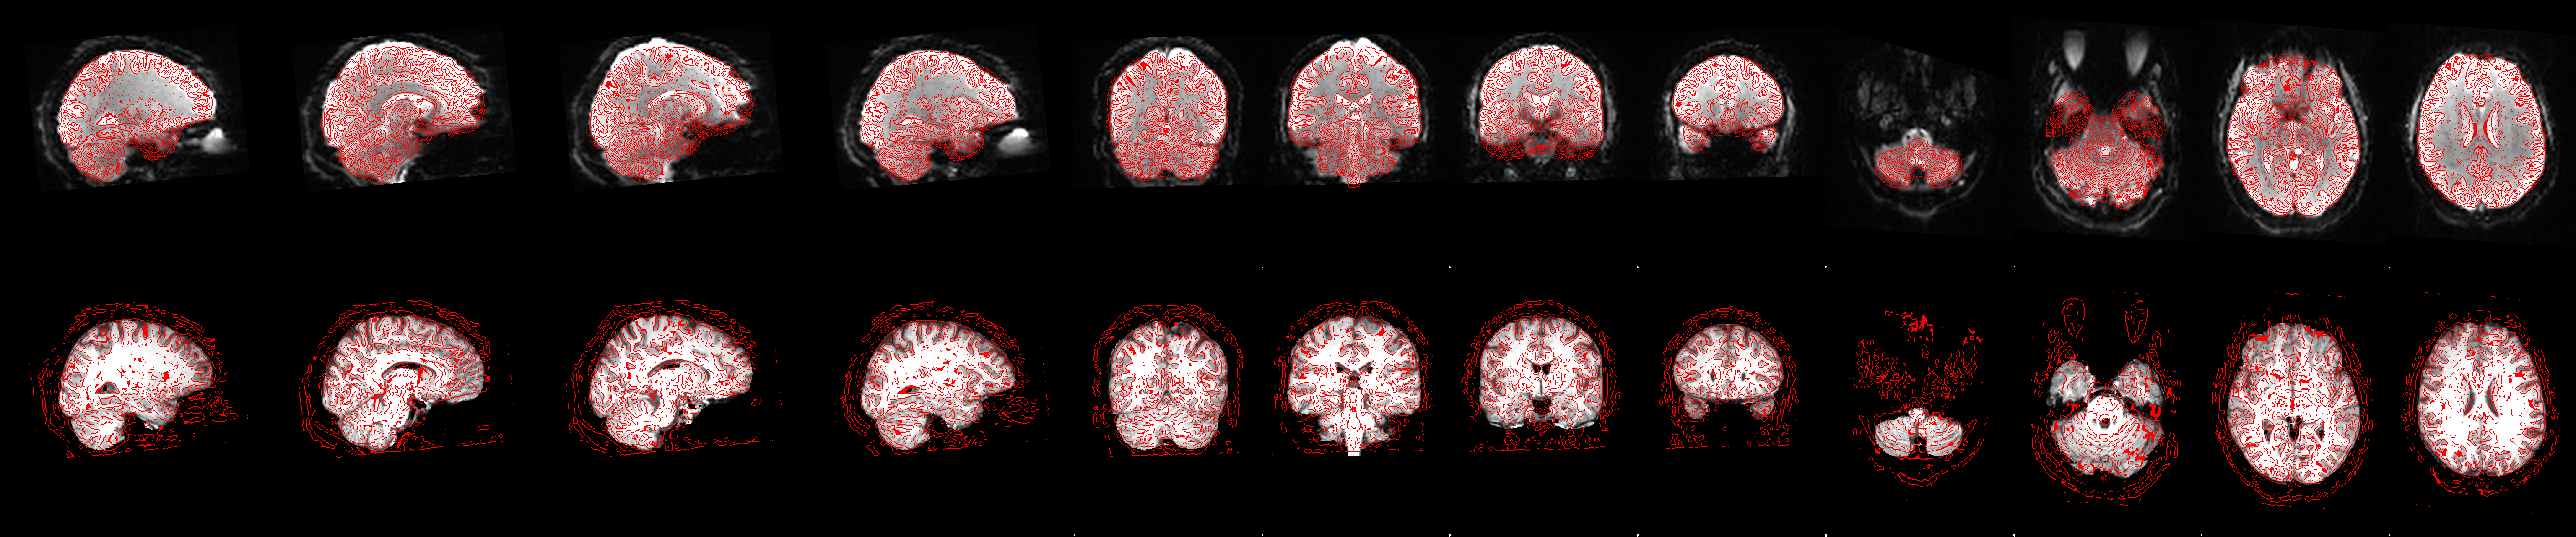

Anatomical pipeline

fsleyes data/RBC/HBN_BIDS/sub-NDARAA306NT2/ses-HBNsiteRU/anat/sub-NDARAA306NT2_ses-HBNsiteRU_acq-HCP_T1w.anat/T1.nii.gz data/RBC/HBN_BIDS/sub-NDARAA306NT2/ses-HBNsiteRU/anat/sub-NDARAA306NT2_ses-HBNsiteRU_acq-HCP_T1w.anat/T1_fast_pveseg.nii.gzEstimation of volumes of regions defined from an anatomical atlas.